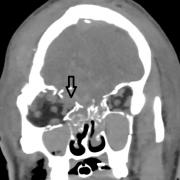

- Accurately identify fractures using CT and 3DCT radiographic findings to prescribe the appropriate treatment required for midface and zygoma fractures.